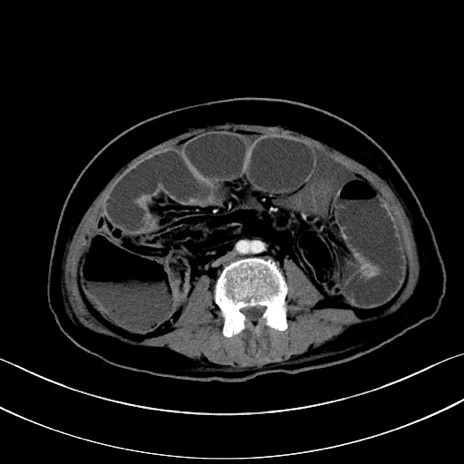

症例28(横断像)

【症例】60歳代男性

【主訴】嘔吐

【現病歴】胃癌にて胃全摘後。食思不振が悪化し、夜中に嘔吐することがある。

【既往歴】胃癌、胃全摘、脾摘、胆摘後

【データ】WBC 5900、CRP 10.56